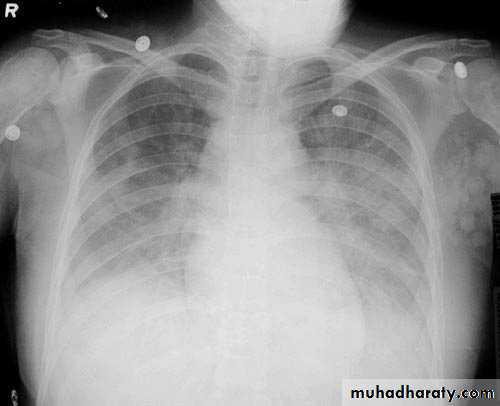

Interstitial pulmonary edemaCXR of adult , PA view shows:Bilatral patchy opacity involving mainly lower lung fields with enlargement of cardiac shadow